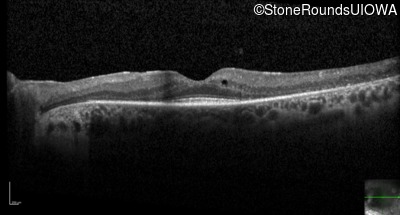

Optical Coherence Tomography - Right - 20/32

Exemplar / OCT Stack

OCT Stack